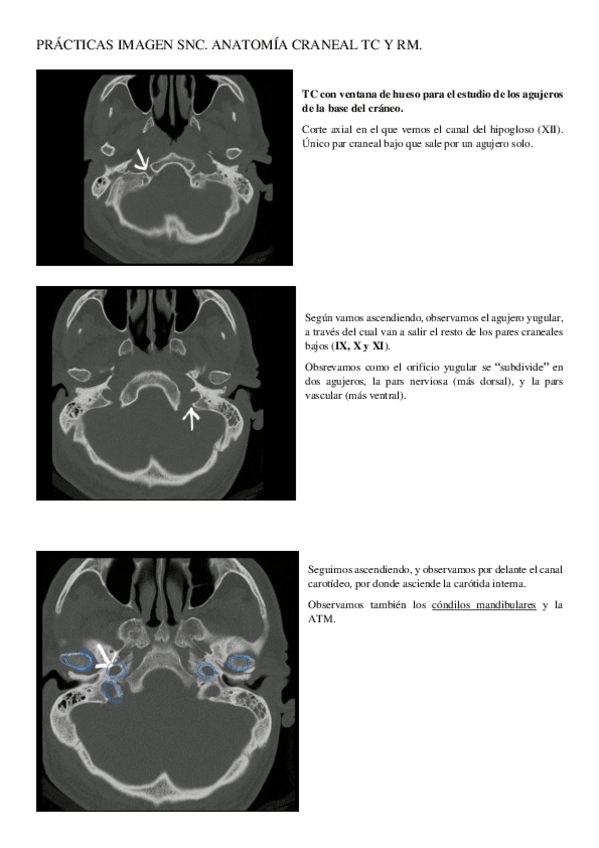

ANAtomia-SNC-practicas.pdf

PRACTICAS-IMAGEN-SNC.pdf